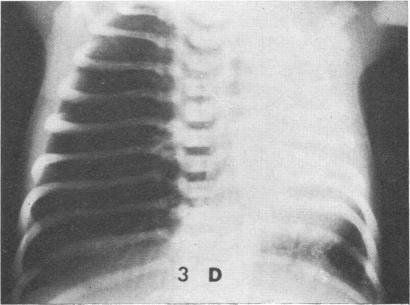

Perlman, M., Williams, J., Hirsch, M., and Bar-Ziv, J. (1975). Archives of Disease in Childhood, 50, 727. Familial non-cystic fibrosis mucus inspissation of respiratory tract. Two sibs, whose parents are first cousins, have had chronic obstructive airways disease from birth with recurrent otitis media, sinusitis, and mastoiditis. The disease, associated with clinically abnormal mucus, differs from other familial obstructive airways diseases and probably constitutes a new entity.

佩尔曼,M.,威廉姆斯,J.,赫希,M.,以及巴尔-齐夫,J.(1975年)。《儿童疾病档案》,第50卷,第727页。家族性非囊性纤维化呼吸道黏液黏稠症。父母为近亲的两名同胞自出生起就患有慢性阻塞性气道疾病,并伴有复发性中耳炎、鼻窦炎和乳突炎。该疾病与临床上异常的黏液有关,不同于其他家族性阻塞性气道疾病,可能构成一种新的病症。